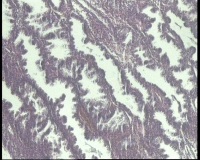

| 图片: | |

- 急!请老师看看34岁子宫内膜

| 性别 | 女 | 年龄 | 34岁 | 临床诊断 | 子宫内膜息肉? |

| 一般病史 | 末次月经:11月20日,近两个月无诱因性生活有阴道少许血性分泌物 | ||||

| 标本名称 | 宫内容物 | ||||

| 大体所见 | 膜样碎组织3.0厘米 | ||||